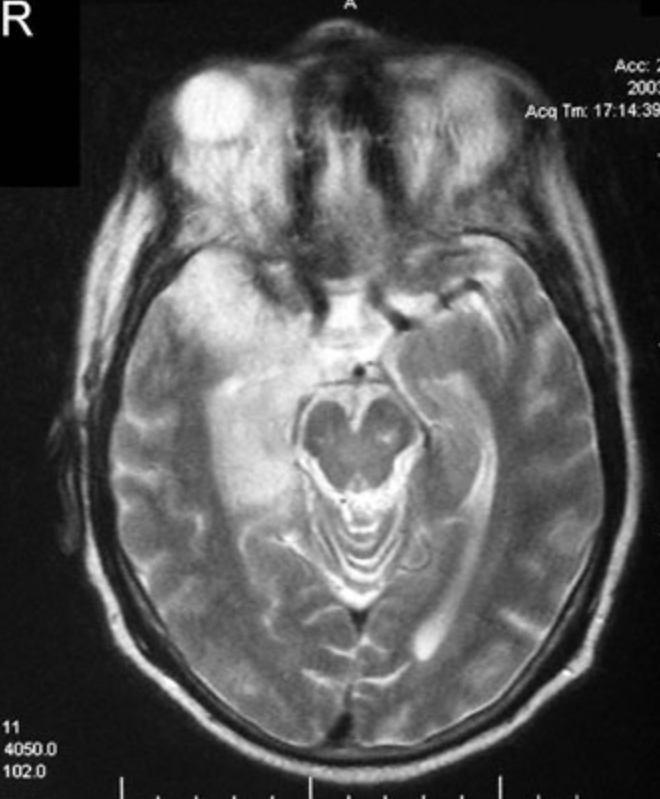

A 38-year-old woman is brought to the emergency department by her husband 30 minutes after she sustained a generalized tonic-clonic seizure. Her husband reports that she has had worsening headache during the past 2 days and had the gradual onset of confusion 1 hour prior to the seizure. The patient has no history of serious illness. Her only medication is an oral contraceptive. She has smoked one pack of cigarettes daily for 20 years. On arrival, she is sleepy but arousable. Her temperature is 37.8°C (100°F). Physical examination shows no abnormalities. On mental status examination, she is oriented to person but not to place or time. She is distractible and recalls zero of three objects after 5 minutes. A T2-weighted MRI of the brain is shown. Which of the following is the most appropriate next step in diagnosis?